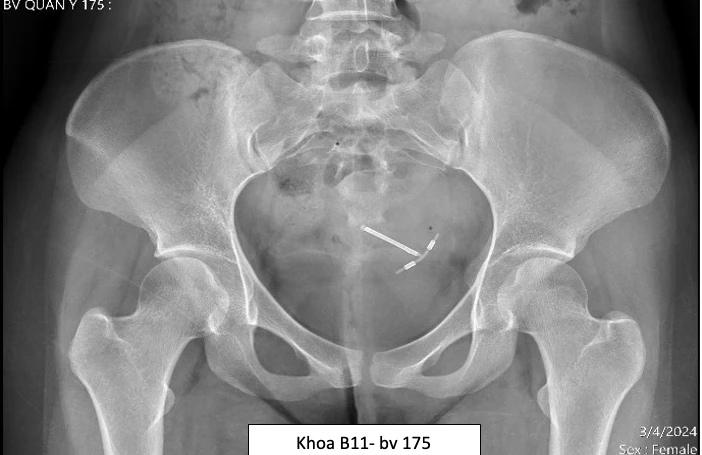

Vòng tránh thai lạc chỗ trên phim X-quang của bệnh nhân NTNY. Ảnh: BVCC

Trường hợp thứ hai là chị NTNY (24 tuổi) mổ lấy thai tháng 9-2022. Sau mổ hai tháng, chị Y đặt vòng tránh thai chứa đồng và không đi khám phụ khoa kiểm tra vòng theo lịch hẹn.

Gần đây chị Y thường xuyên đau bụng lâm râm vùng hạ vị, đi khám kiểm tra tại BV Quân y 175 phát hiện vòng tránh thai chữ T xuyên qua cơ tử cung tại vị trí sẹo mổ đẻ cũ, hai nhánh của vòng dính sát thành bàng quang.